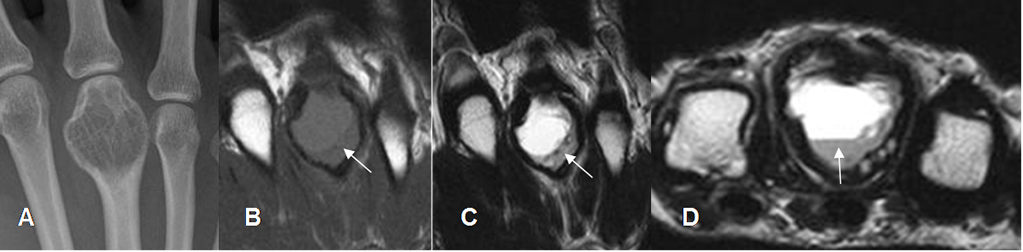

Fig 143. Quiste óseo aneurismático.

A: Rx AP. Lesión expansiva en la zona distal del metacarpiano, de comportamiento benigno.

B: RM coronal en T1, C: RM coronal en T2 y D: RM axial en T2. Imagen quística con nivel líquido/líquido, secundaria a quiste óseo aneurismático.